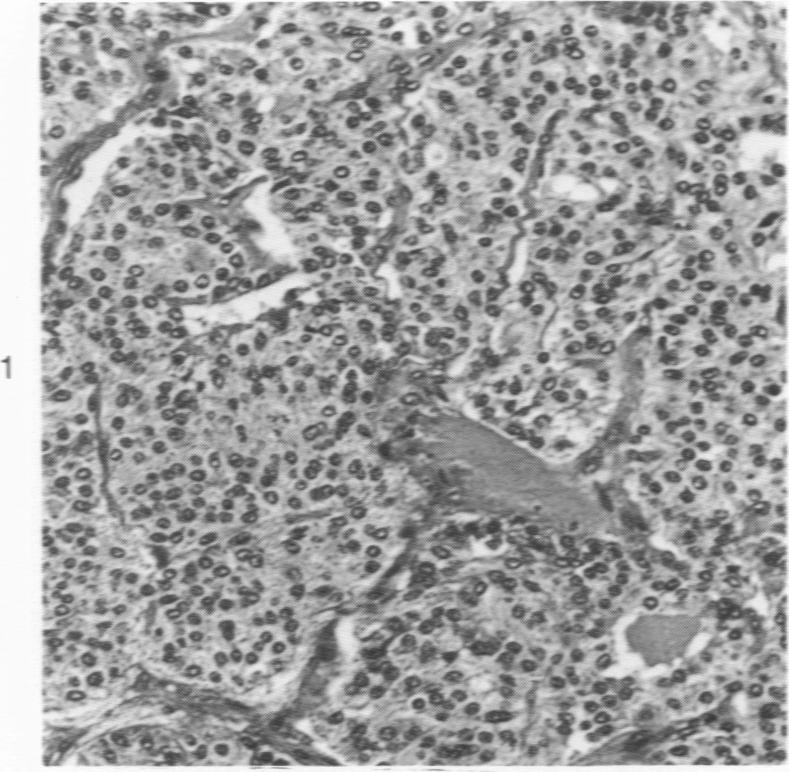

Eighteen cases of medullary carcinoma of the thyroid were analyzed immunohistochemically for calcitonin- and ACTH-containing cells, and tumor cells in 8 cases were examined by an electron microscope and analyzed by manual and computer procedures with particular attention paid to the size and quality of secretory granules. Calcitonin- and ACTH-containing cells were found singly or in clusters in 14 and 11 tumors, respectively. In 4 cases, calcitonin-positive cell clusters and an increase in number of singly scattered C cells were seen apart from the main tumor, suggesting a multicentric nature of certain medullary carcinomas. Some ACTH-containing cells were apparently also positive for calcitonin. In a case of familial Sipple disease, follicular lining cells were replaced in areas with ACTH-containing cells. Three to five frequency distribution curves of the size of secretory granules were obtained in all of 6 cases analyzed, and at least two different types of granule matrix were identified.

对18例甲状腺髓样癌进行免疫组织化学分析,以检测降钙素和促肾上腺皮质激素(ACTH)细胞,并对其中8例肿瘤细胞进行电子显微镜检查,同时采用手工和计算机程序进行分析,特别关注分泌颗粒的大小和质量。分别在14例和11例肿瘤中发现了单个或成簇的降钙素细胞和ACTH细胞。在4例中,除主要肿瘤外,还可见降钙素阳性细胞簇和单个散在C细胞数量增加,提示某些甲状腺髓样癌具有多中心性。一些ACTH细胞显然也对降钙素呈阳性反应。在一例家族性西普尔病中,滤泡衬里细胞部分被ACTH细胞取代。在所有分析的6例中均获得了三到五条分泌颗粒大小的频率分布曲线,并且鉴定出至少两种不同类型的颗粒基质。